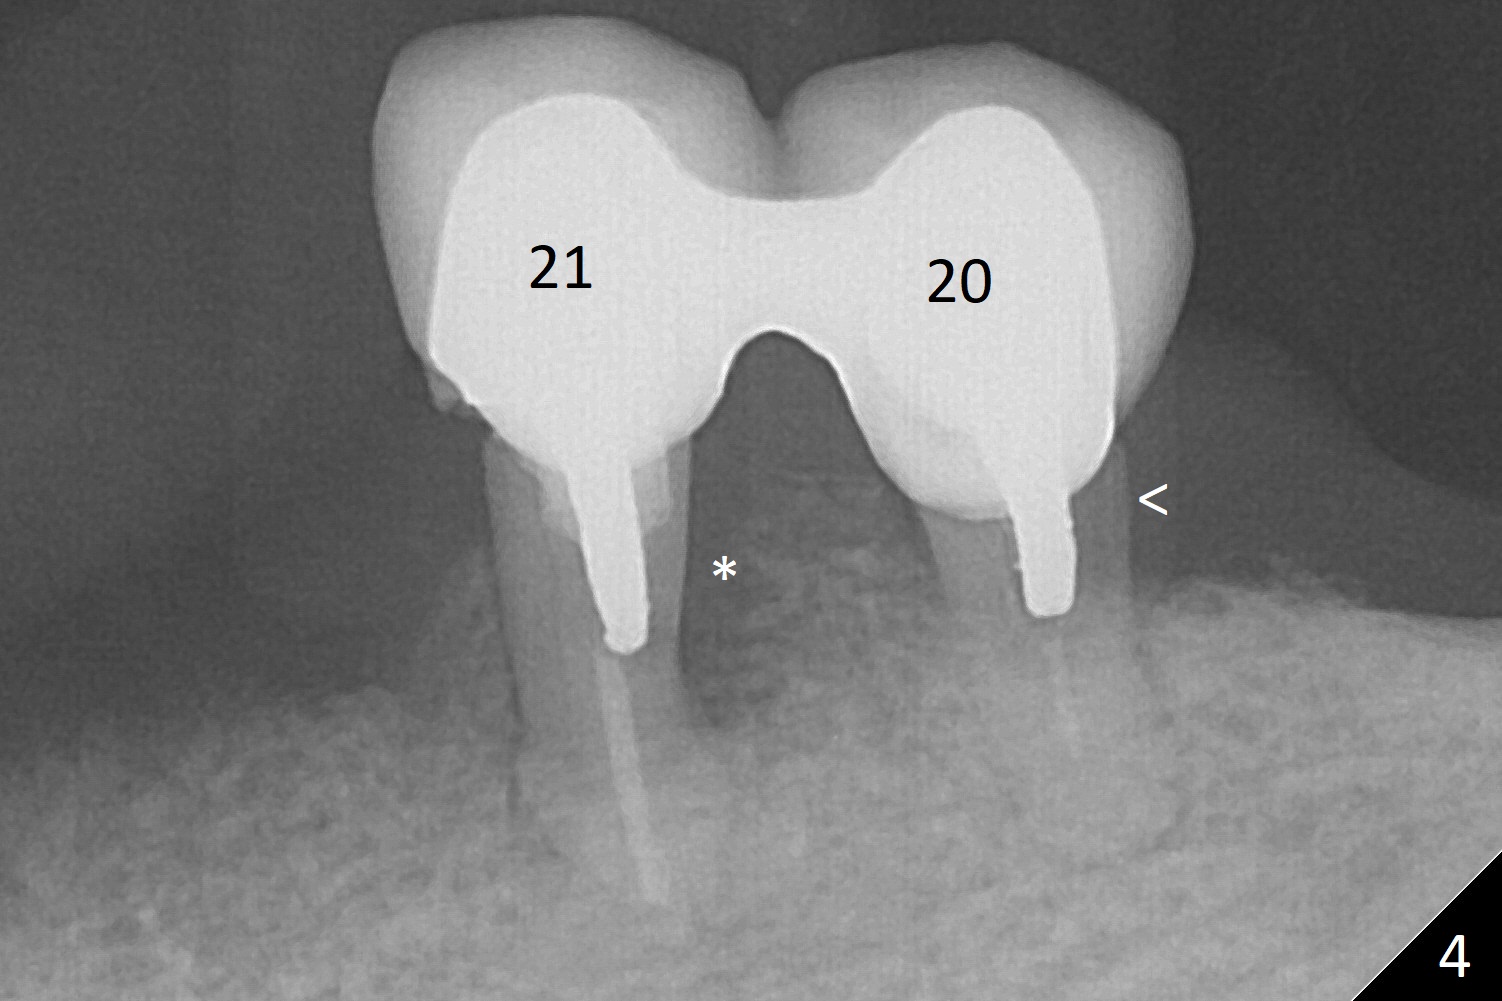

A 62-year-old woman has failed implant at #27 for the 2nd time. The crowns at #20 and 21 are loose and non-salvageable (Fig.4-6). Three implants will be placed at #20, 21 and 28 (Fig.1), since the bone height in the lower right posterior region is limited. Ball abutments will be used to retain the lower RPD. When a narrow implant is placed at #28, it will invade the Incisive Canal (Fig.2 red circle), which does not cause neuropathy, but hemorrhage. In contrast, it is safer to place a 2 mm 1-piece implant with ball type after ridge reduction (Fig.3 black triangle).

At #20 and 21 (Fig.5,6), immediate implants (2 piece) will be placed, although there is possibility of place a 1-piece one at #21 (Fig.5).